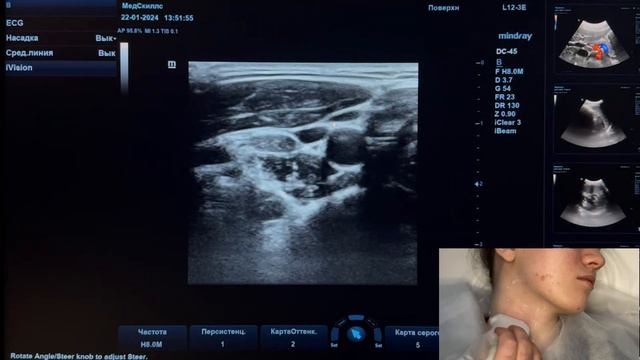

Узи лимфоузлов отзывы